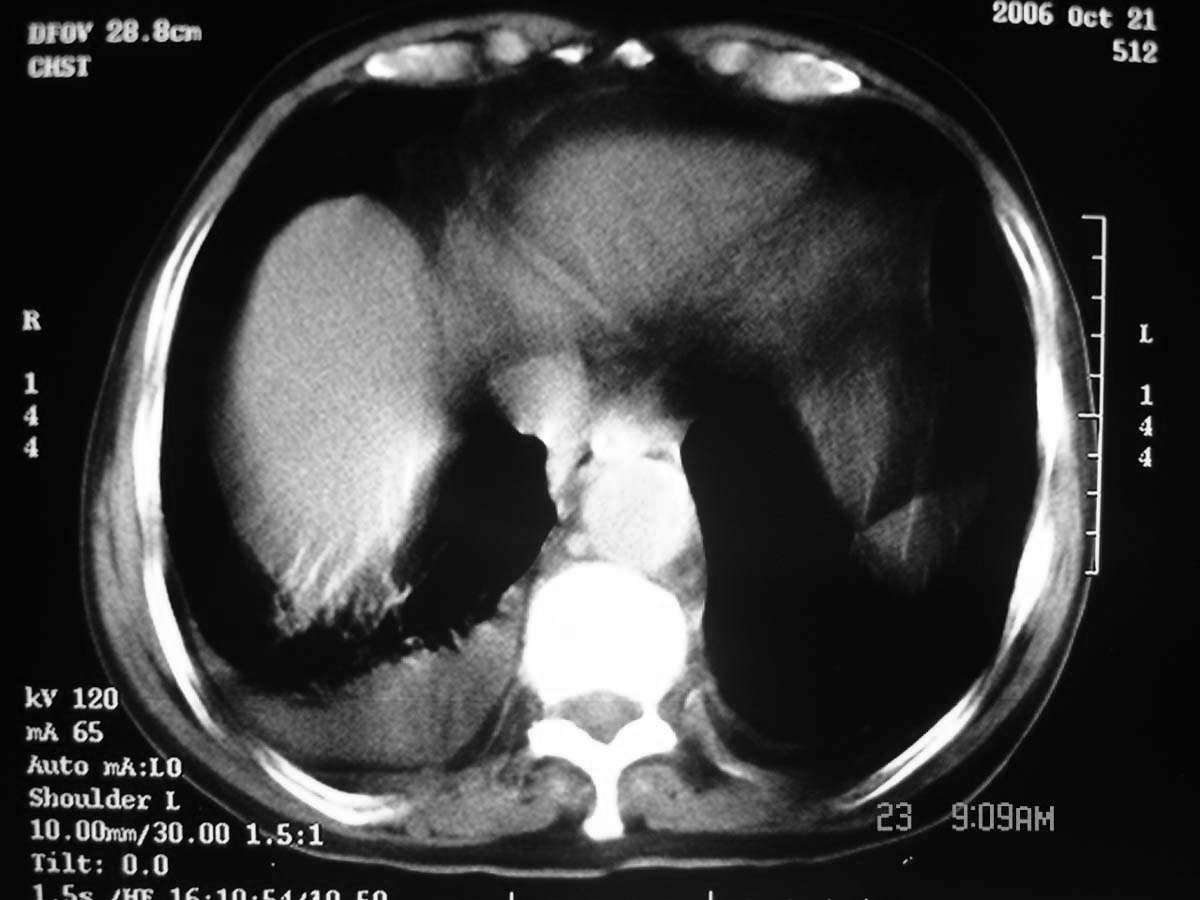

以下是引用守望可可西里在2006-11-23 14:33:00的发言:[br][br] 糖尿病病人很容易继发结核,病人又有双侧胸膜增厚、粘连、胸腔积液以及双上肺的斑片状、条索状影结核病灶影,以一元论考虑,右下肺病变首先考虑干酪性肺炎,可以正规抗炎治疗后复查,排除一般的肺炎。